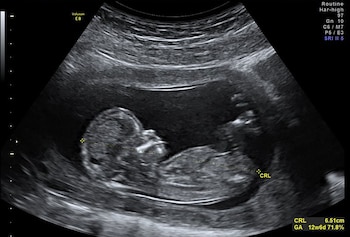

La gastrosquisis es una condición rara pero grave que se detecta desde la semana 12 de gestación. Consiste en un defecto de la pared abdominal del feto que permite que los intestinos —y en ocasiones otros órganos— salgan hacia el exterior, quedando expuestos al líquido amniótico. Afecta entre 4 y 7 de cada 10.000 nacimientos vivos y, sin tratamiento adecuado, puede derivar en complicaciones como el síndrome de intestino corto, una afección que impide la adecuada absorción de nutrientes y puede requerir alimentación intravenosa prolongada o incluso trasplantes.